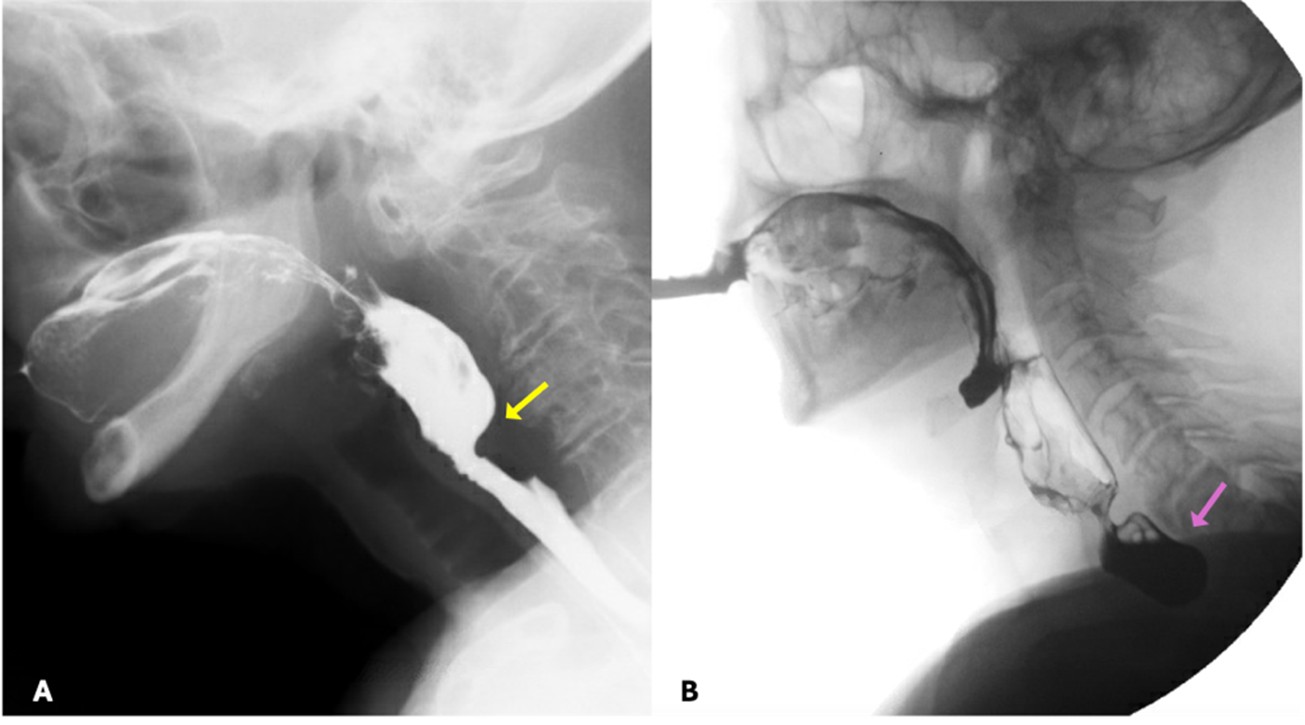

Penetration and aspiration can be classified according to the timing of their occurrence, which helps to identify the underlying causal mechanism. When there is incomplete closure of the larynx or delayed triggering of the swallow reflex, contrast enters the airway during the pharyngeal phase of deglutition. Aspiration can also occur before the pharyngeal phase of deglutition, typically in the setting of posterior escape from the oral cavity or poor coordination in oropharyngeal bolus transport. On the other hand, aspiration can also occur after the pharyngeal phase of deglutition when there are persistent pharyngeal residues that can spill into the airway when the larynx opens - this occurs when pharyngeal clearance is hindered by insufficient contraction of pharyngeal muscles, incomplete opening of the upper oesophageal sphincter or presence of obstructive masses. (Fig. 11)

Figure 11: Range of underlying causes for compromised airway protection. (A) Posterior bolus escape from the oral cavity resulting in laryngeal penetration before the pharyngeal phase of deglutition; (B) Aspiration of contrast during the pharyngeal phase of deglutition due to delayed triggering of the swallow reflex; (C) Persistent pharyngeal residues that resulted in the aspiration seen in the panel B of figure 10